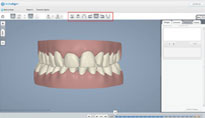

诺贝尔速导种植系统设计过程完全“可视”